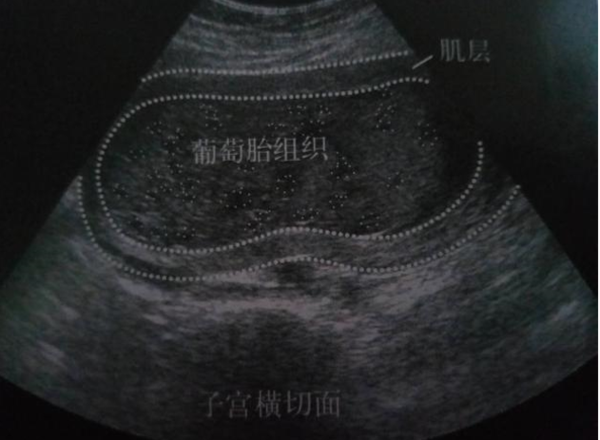

什么是葡萄胎

葡萄胎是妊娠时,由于受精卵出现异常致使的一种疾病。此时孕妇胎盘上的细胞不断增生,出现水肿现象,最后形成大小不一像葡萄一样的水泡,这就是葡萄胎。

1、完全性葡萄胎:全部胎盘绒毛发生水泡异变,胎儿没有形成,也没有胎儿附属物,子宫内腔全部都是水泡。

2、部分性葡萄胎:部分胎盘异变,子宫内还有存活的胚胎或者已死。需要注意的是,在自然流产中有百分之四十的孕妇是水泡异变,而不是葡萄胎。